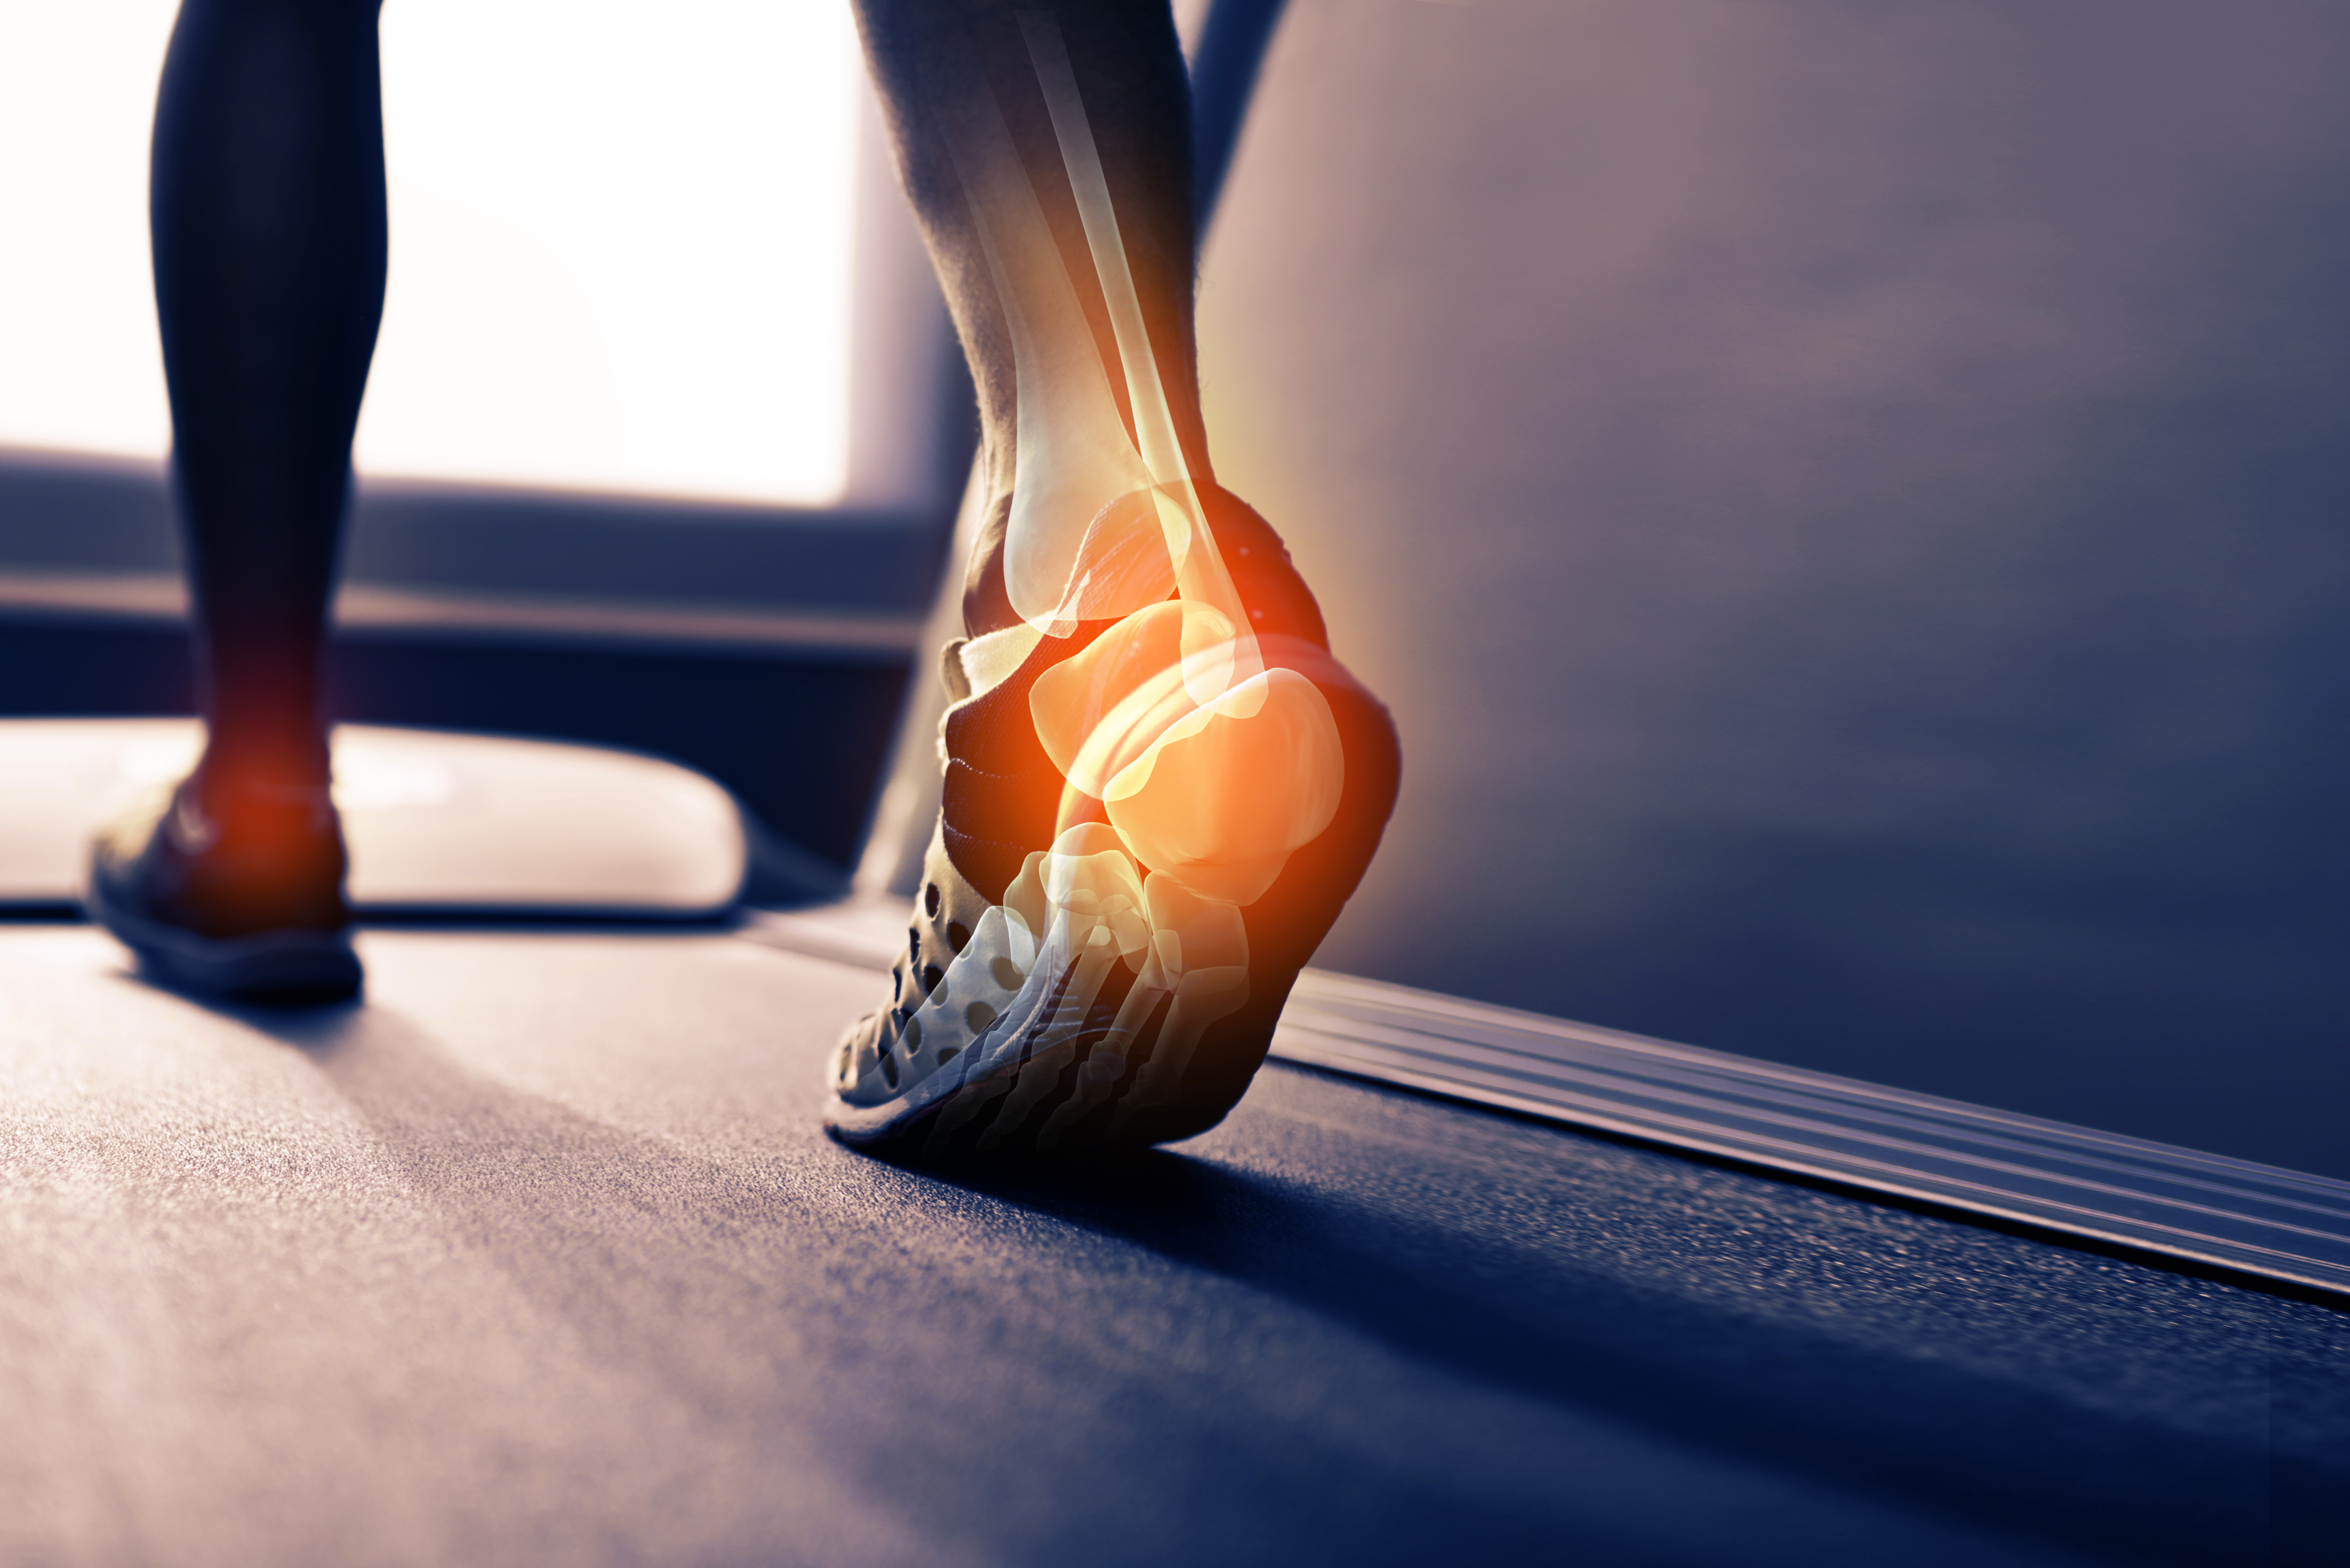

Fractured heel pain clearance

Fractured heel pain clearance, Calcaneal Stress Fracture How to differentiate stress fractures clearance

Fractured heel pain clearance

Calcaneal Stress Fracture How to differentiate stress fractures

Product Name: Fractured heel pain clearance